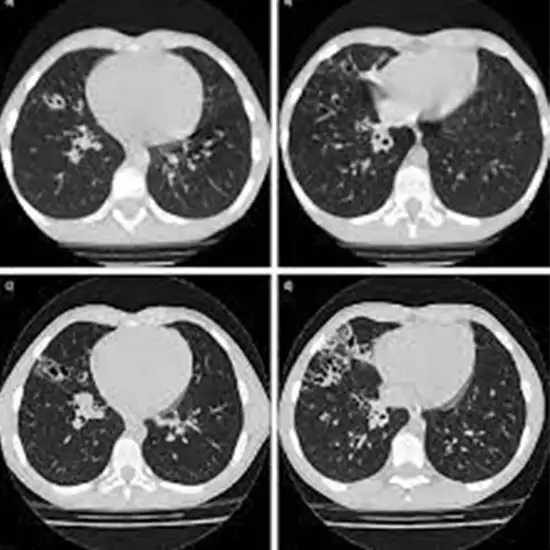

Plain HRCT (High-Resolution Computed Tomography) refers to a CT scan that produces a more precise cross-section image of the lungs than a standard chest CT. An HRCT scan of the chest is an imaging procedure that uses narrow X-ray beams to produce a high-resolution image of the lung anatomy. This test is used to evaluate lung function, detect abnormal growth in the lungs, and detect obstructions to airflows through the lungs.